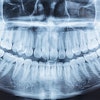

The use of cone-beam computed tomography (CBCT) in younger pediatric patients has risen every year since 2017, indicating increased awareness about the uses of the imaging modality. The study was published on January 19 in the International Journal of Paediatric Dentistry.

There was an increase in the number of scans in patients between the ages of 6 and 12 between 2017 and 2020. Most often, imaging was ordered to assess dentigerous cysts and impacted teeth. Since it is important to master the use of CBCT in pediatric patients in the right indications, clear, thorough guidelines for the use of CBCT in children are needed, the study's authors wrote.

To explore the use of CBCT in pediatric dentistry, the authors evaluated 334 CBCT scans taken at different times and for distinctive reasons in 319 patients.

In the 6-12 age group, 85 CBCT scans were taken between 2017 and 2020, while 249 scans were completed in the 12-18 age group. During that time period, the number of CBCT scans of children ages 6 to 12 increased every year, while those in the older age group underwent the most scans, according to the study.